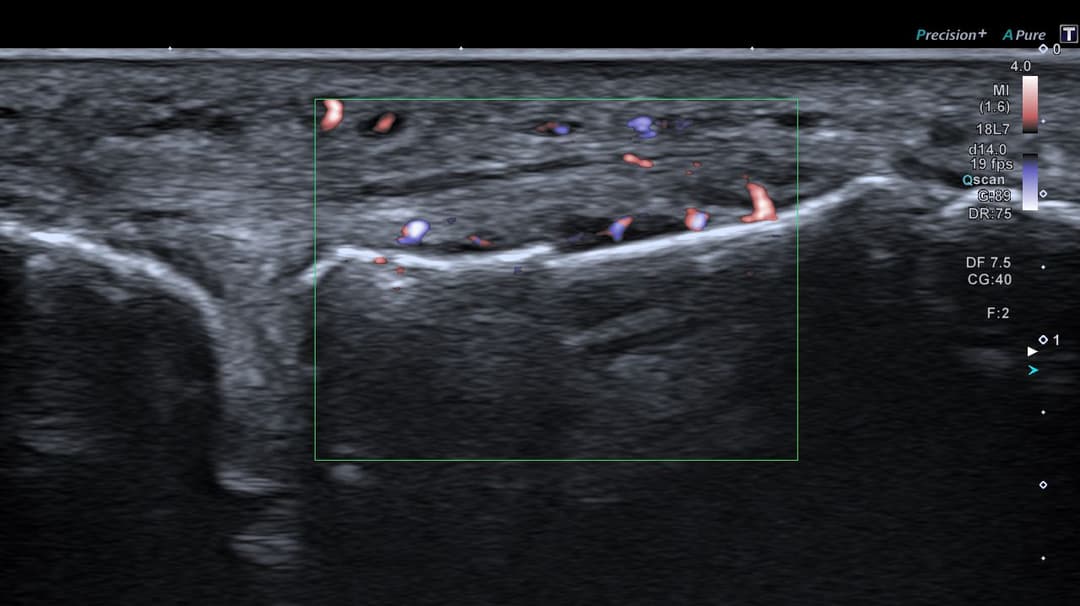

Échographie

Fracture instable étudiée en échographie dynamique